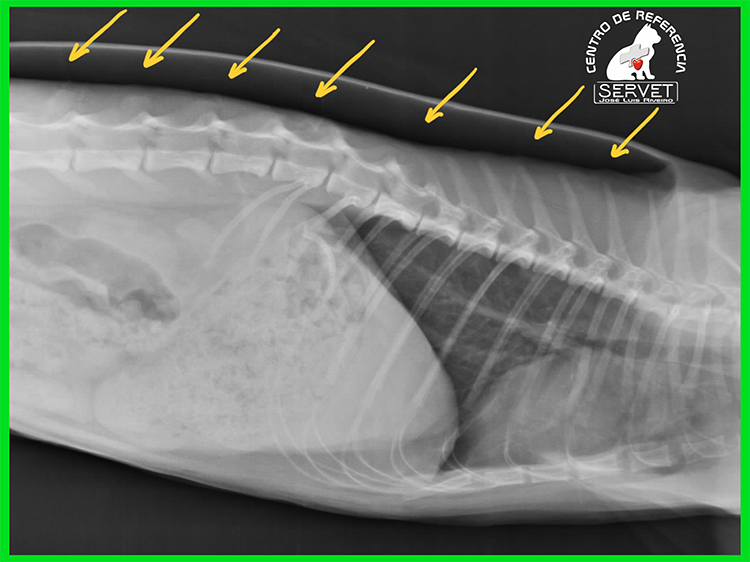

En la imagen superior puede verse el aire acumulado inmediatamente por debajo de la piel (flechas amarillas). En la foto puede verse al animal inmediatamente después de la cirugía de reparación del pulmón y la pared costal.